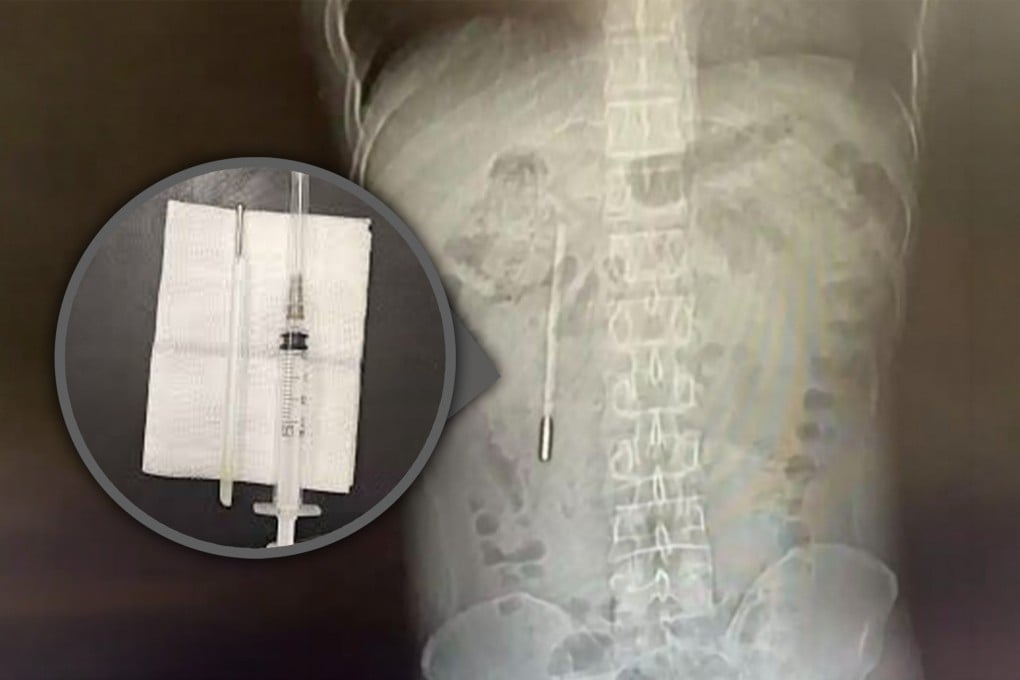

A scan revealed a foreign object in his duodenum, which doctors highly suspected to be a mercury thermometer.

As the tip of the thermometer was pressing directly against the intestinal wall, it posed a high risk of perforation and severe internal bleeding.